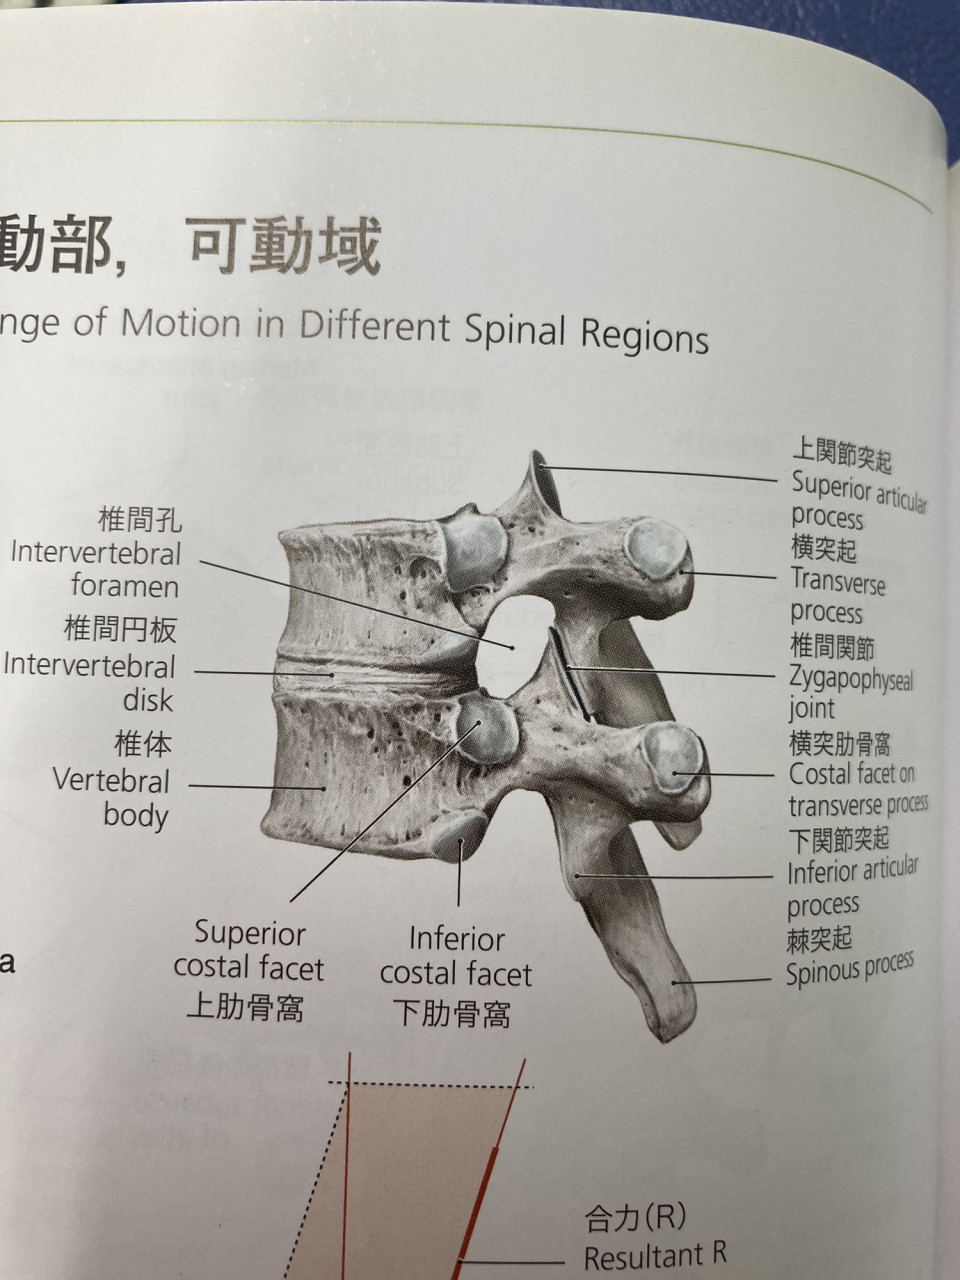

椎間関節とは腰椎の安定化をさせるための関節でして腰椎が後方移動、回旋動作を止める役割があります。

特徴としては侵害受容器(刺激を感じるセンサー)が豊富にあるということです。 つまりある刺激を加えると痛みを感じやすいということです。

その関節が痛みを拾っているのが椎間関節の痛みというわけです。 主に反り腰さんや、体幹機能の低下してる方や女性に多いです。

椎間関節には多裂筋という筋肉が付着しておりその筋肉が過剰に収縮して痛みを引き起こすこともあります。

椎間関節だけが傷んでいる場合もありますし、多裂筋が問題として引き起こす場合も、両方悪い場合もあります。

原因を見極め対処することが大事になります。

治療で大切なのは負担部分をゆるめる、滑走を改善するが有効です。

しかしそもそも反り腰さんの場合は椎間関節に常にストレスがかかっているので反り腰を改善しないと根本的な解決には至りません。

アライメントの改善にドローインや体幹のトレーニングが必要となります。